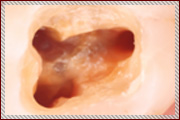

写真で見る、顕微鏡を用いた根の治療

お口の中は通常この様に暗く、目視だとなかなか細部までは見えません。

特に歯の根っこはとても複雑になっていているため、目視のみの治療には限界があります。 -

当院では顕微鏡を用いて上記のサイズに拡大して、細かい歯の根っこの治療を行いますので、神経を傷つけずに、リスクの少ない治療を心がけております。